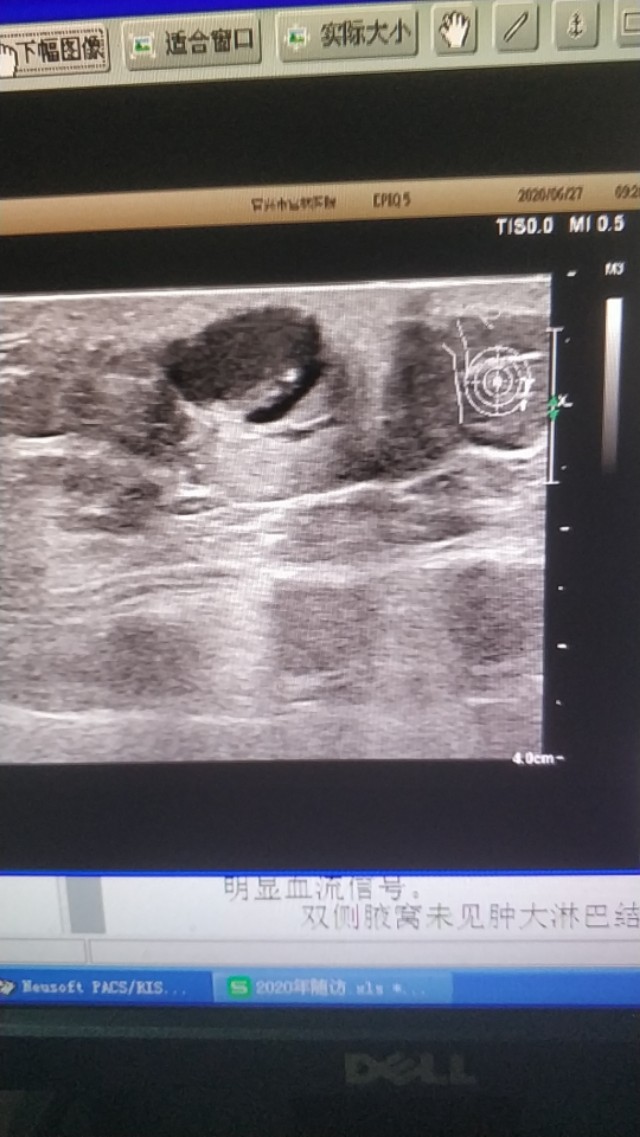

上面是一张胸壁的表皮囊肿,边缘不光滑,下方有液性暗区,这是一个表皮囊肿破裂的病例的。

(这两个病例是上个月随访的)